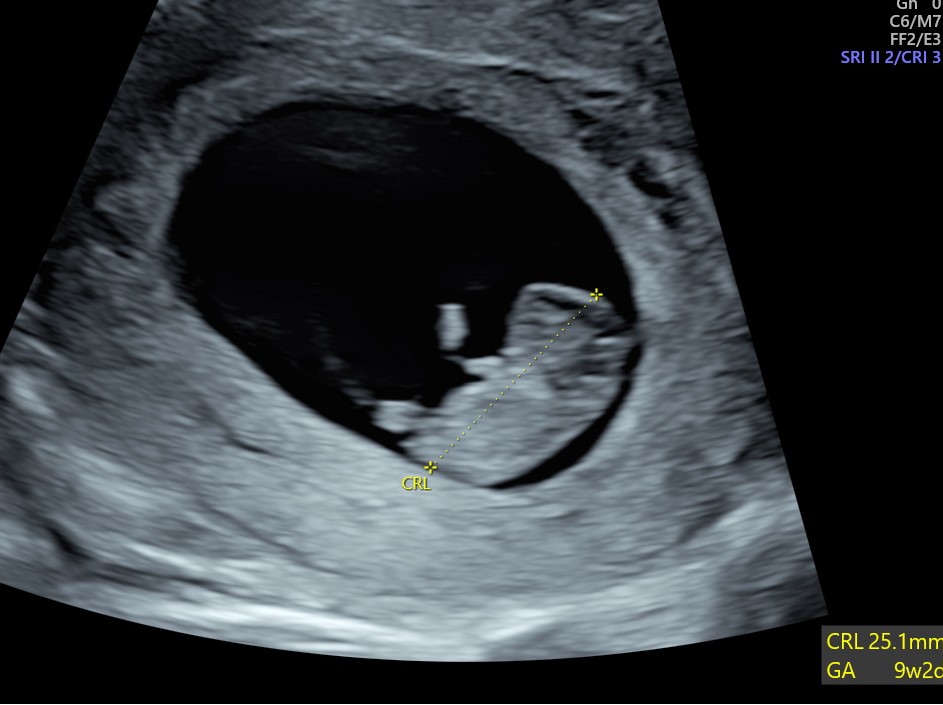

A gestation sac with a yolk sac and a foetal pole (baby) with a heart beat. We can measure the foetal pole to date the baby.

Early Pregnancy 6 – 12 weeks – (recommend to book nearer 7 wks to ensure seeing the baby) £75